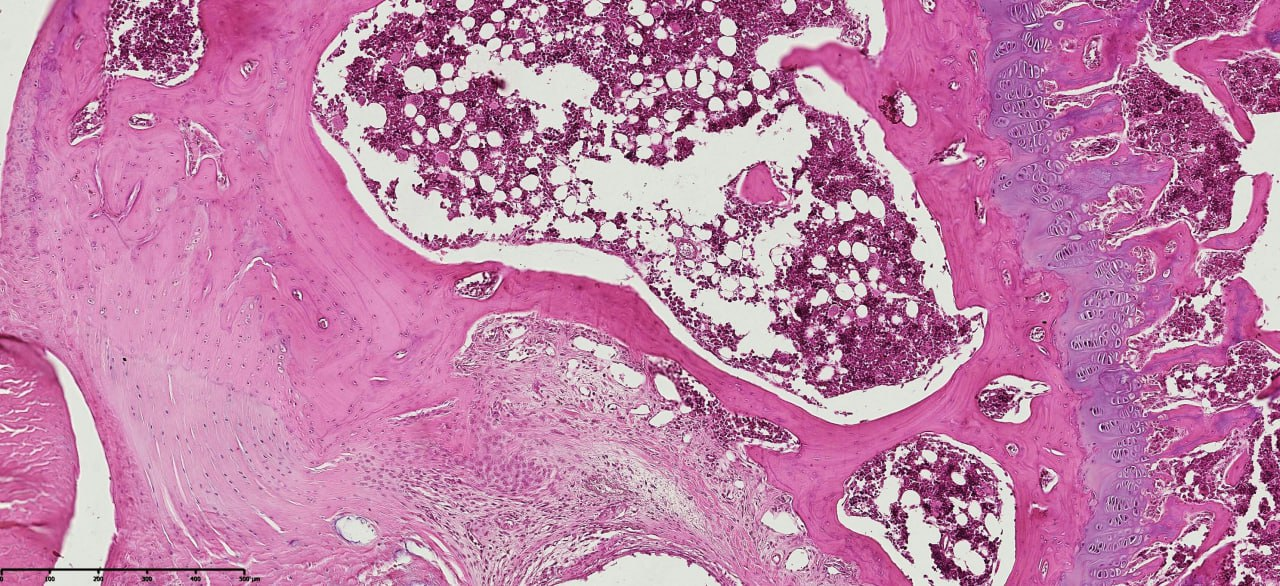

Histopathological evaluation of meniscus samples from patients with post-traumatic gonarthrosis demonstrated prominent and region-specific degenerative alterations consistent with advanced meniscal pathology. On gross examination, the menisci showed surface irregularities, fragmentation along the inner border, and contour deformities, especially in the posterior horn, which is exposed to higher mechanical forces.Microscopically, there was substantial disruption of the collagen fiber network and extracellular matrix (ECM) structure. The collagen fibers exhibited disordered alignment and fragmentation, with circumferential and radial fibers irregularly oriented, impairing normal load transmission and shock absorption. Proteoglycan accumulation was detected in degenerated areas, indicating active matrix remodeling and changes in tissue biomechanics (see figure 1). | Figure 1. Histopathological section of the meniscus from a patient with post-traumatic gonarthrosis showing surface irregularities, inner border fragmentation, and disorganized collagen fiber network. Proteoglycan accumulation is visible in degenerated regions. Tissue section stained with hematoxylin and eosin (H&E). Magnification: 20x10. Scanned using NanoZoomer (REF C13140-21, S/N000198, HAMAMATSU PHOTONICS, Japan) |